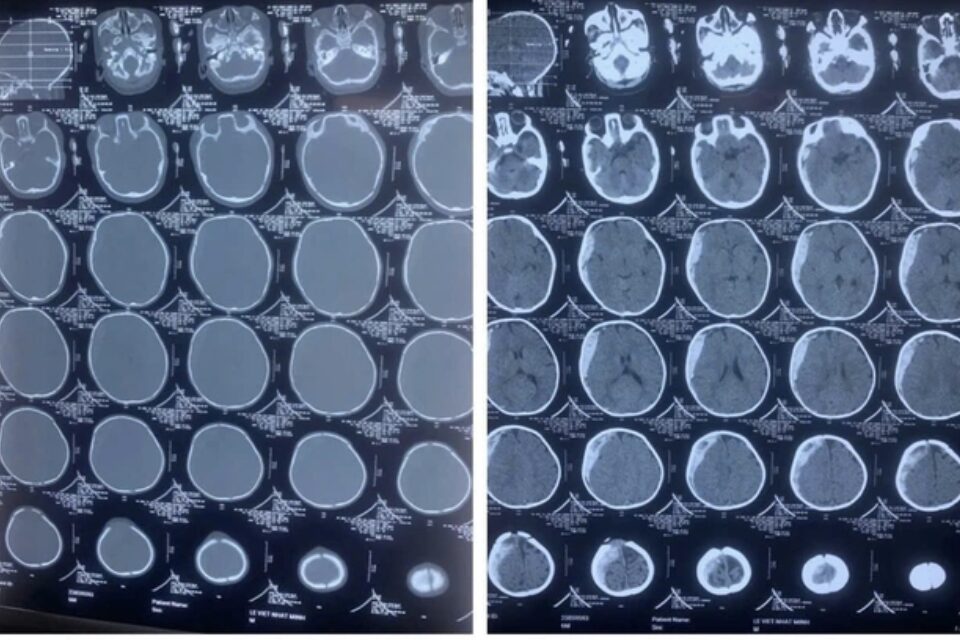

Mới đây, Khoa Ngoại Chấn thương, Bệnh viện Trẻ em Hải Phòng đã tiếp nhận bệnh nhi nam 6 tháng tuổi vào cấp cứu trong tình trạng hôn mê, thở máy. Trẻ được chụp CT scan cắt lớp sọ não, phát hiện có tụ máu dưới màng cứng lượng lớn, có chèn ép não vùng bán cầu não phải.

Kết quả chụp CT Scanner cắt lớp sọ não thấy có hình ảnh tụ máu dưới màng cứng lượng lớn, có chèn ép não vùng bán cầu não phải (Ảnh: BVCC)